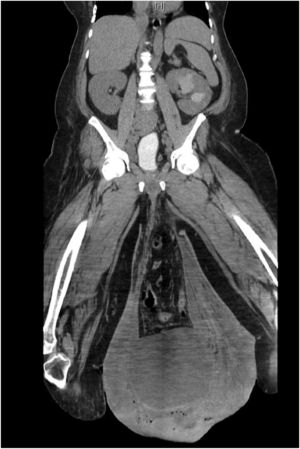

When he arrived at the hospital, he had a fever of 102.2 °F (39 °C) and rapid heart rate, as well as extensive swelling and thickened skin in his scrotum and upper right leg. He also had two open wounds in his scrotum. Further imaging of his abdomen and pelvis revealed a large hernia containing part of his colon, as well as a huge abscess, considerable tissue damage, and fluid collection. (You can see NSFW images of his condition here)